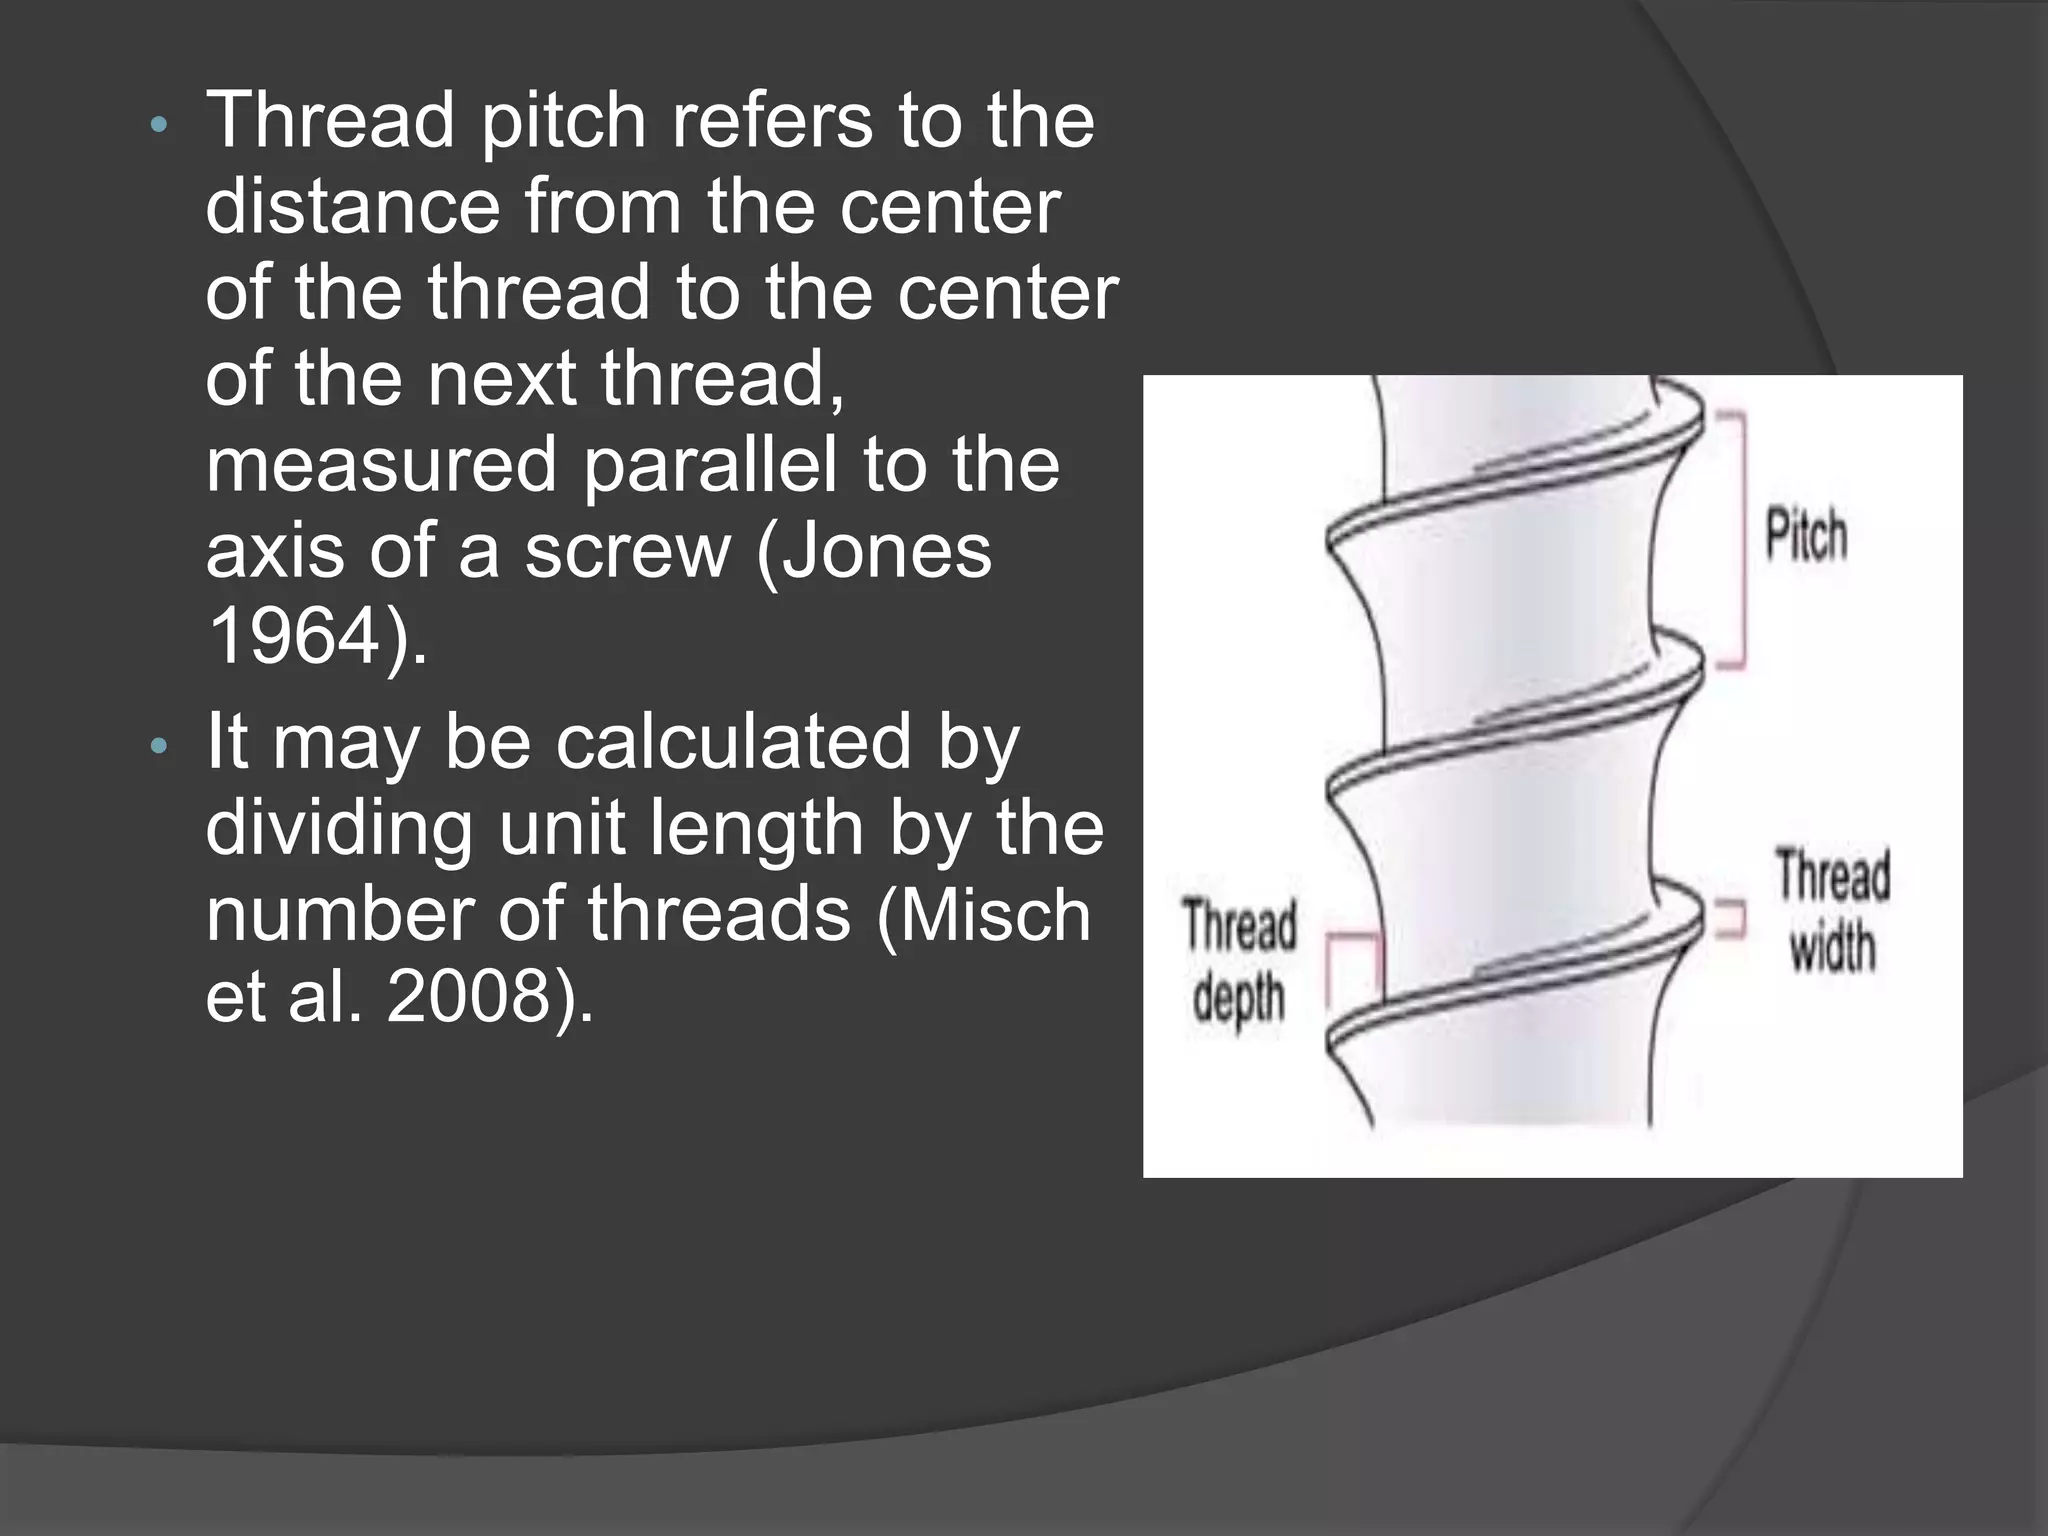

This document discusses factors that influence osseointegration and primary stability of dental implants, including implant design characteristics, surgical technique, and loading protocols. Specifically, it covers the processes of osseointegration and how forces on implants can either promote or inhibit bone remodeling. Key implant design considerations like length, diameter, threads, coatings and surface topography are analyzed in terms of their effects on stress distribution and bone-implant contact. The importance of primary stability and factors influencing it like bone quality and surgical skill are also addressed. Loading protocols ranging from immediate to conventional loading are compared.